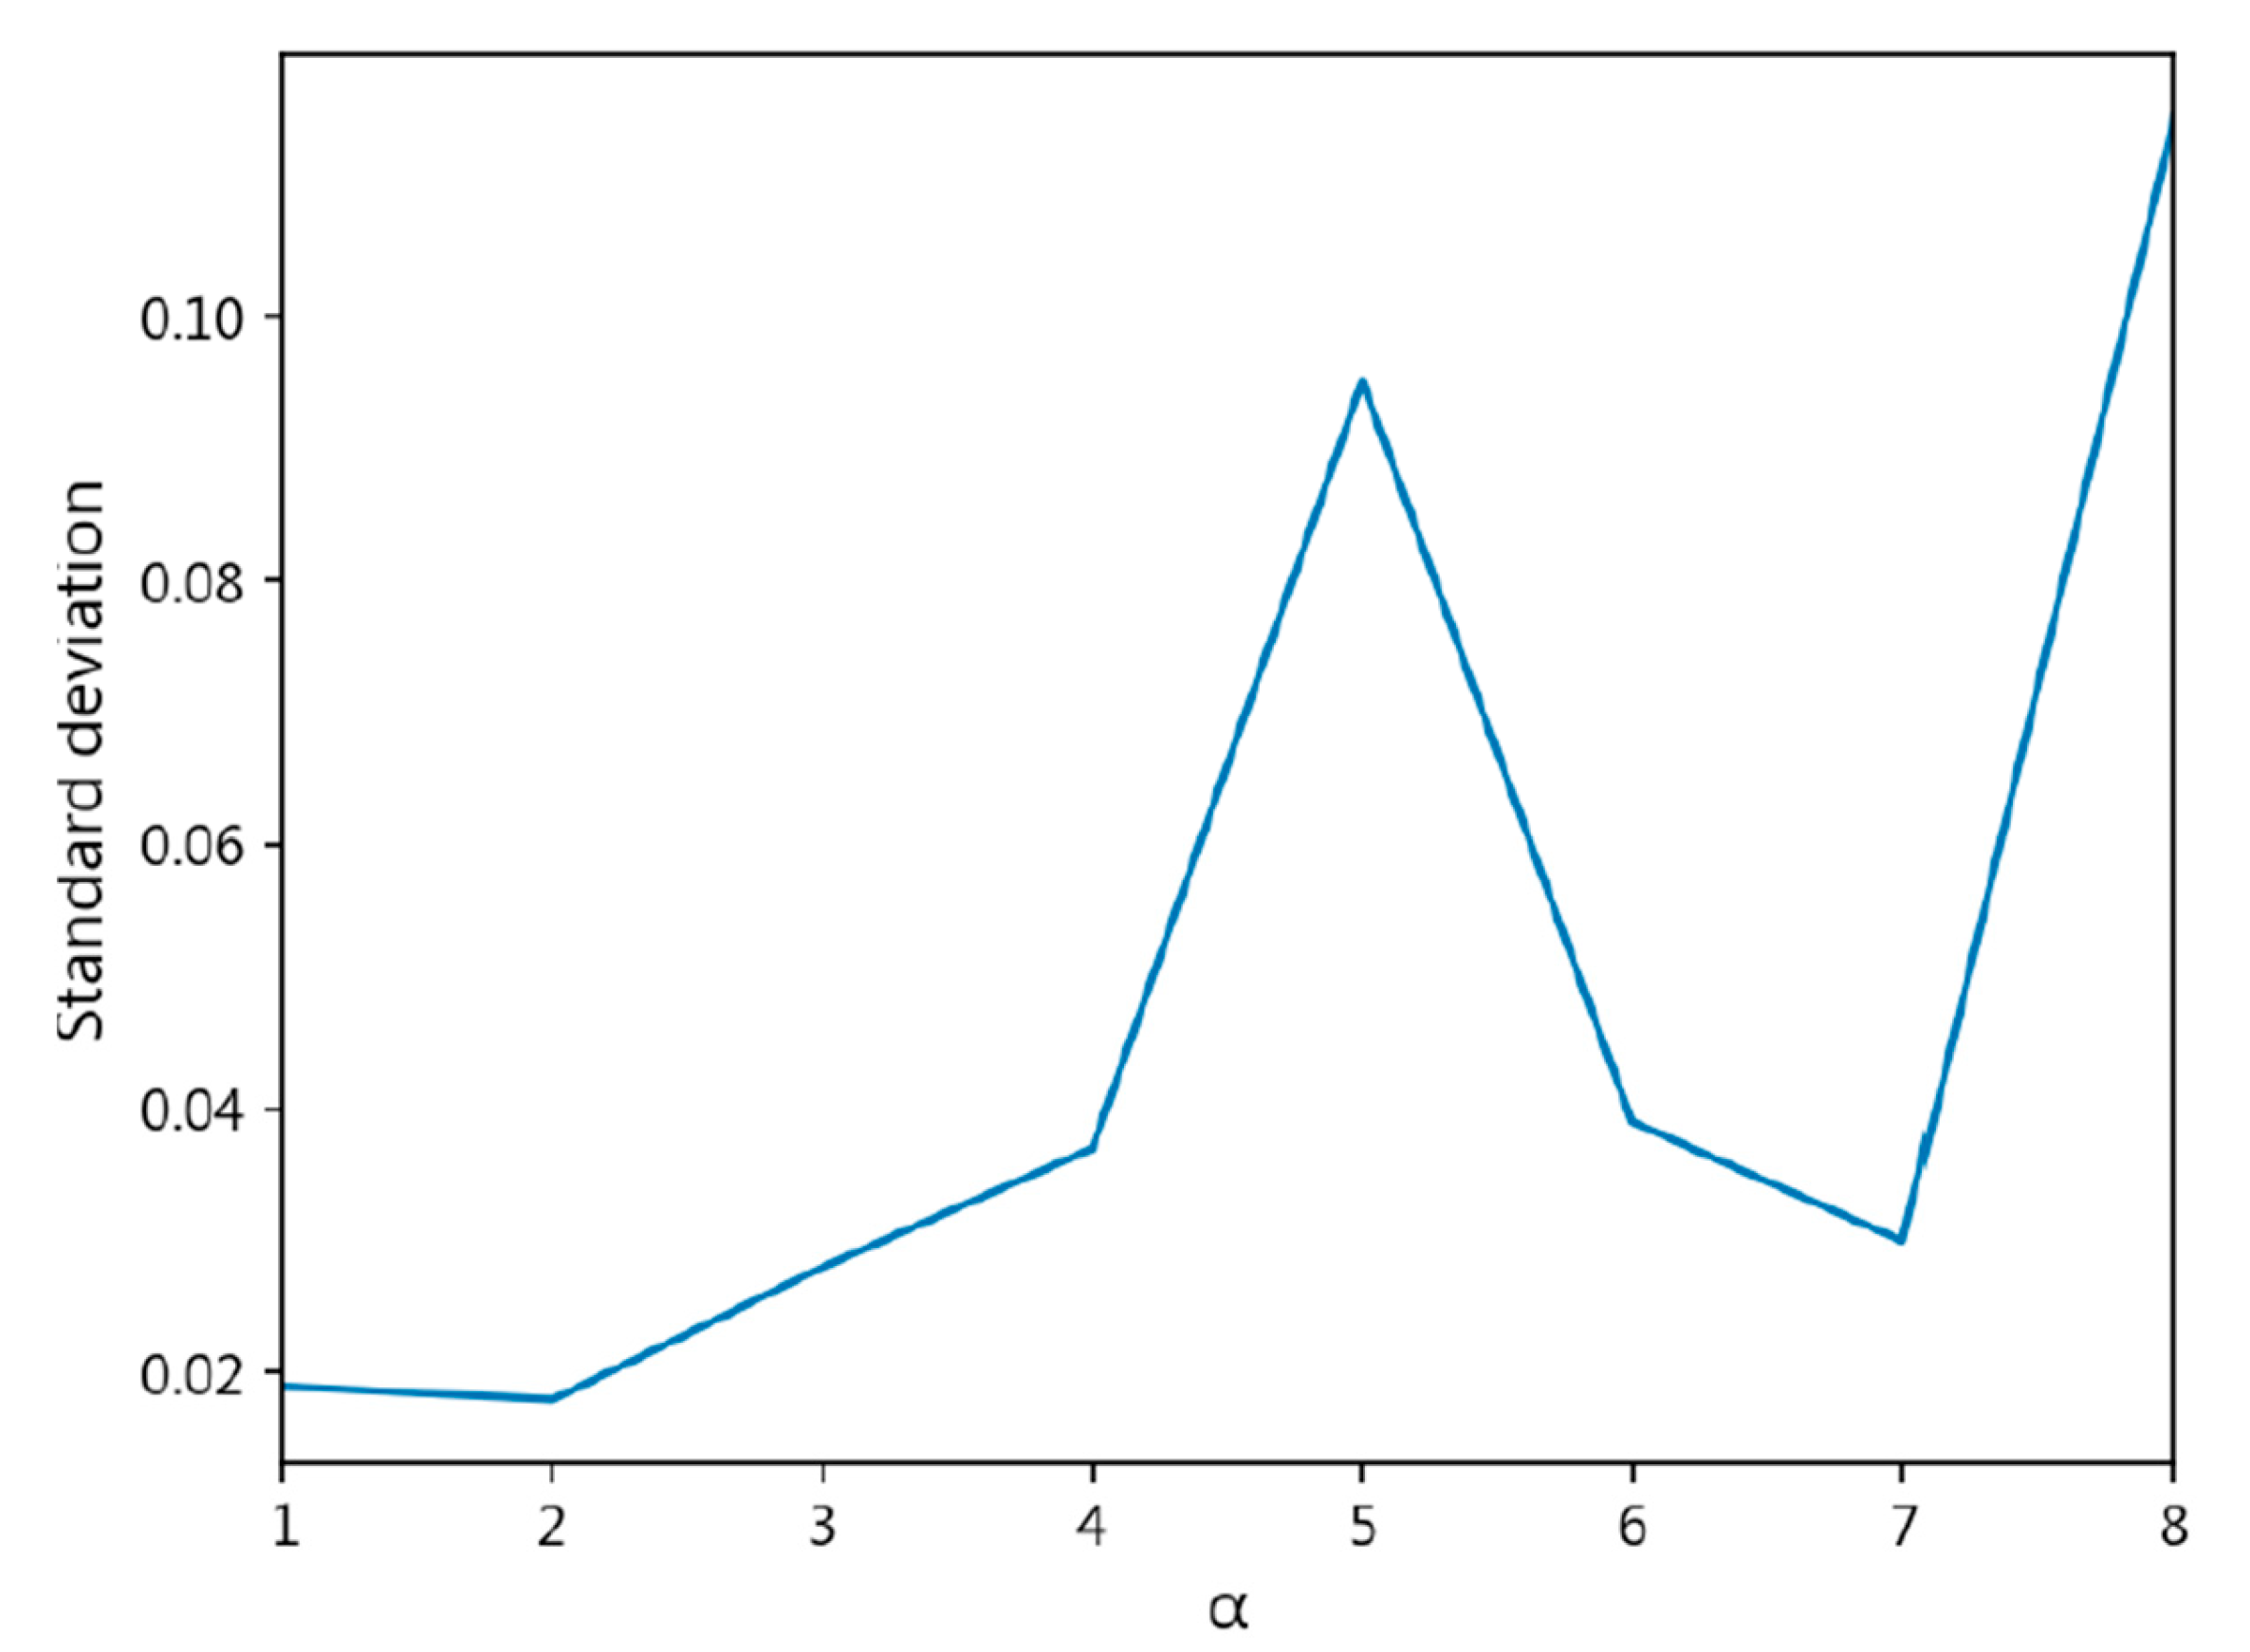

- The exponent a in the CDW-CE formula requires manual tuning of different values, making the process more time-consuming. Additionally, as a increases, the penalty intensity also increases, leading to higher loss values and longer training times.

- Through cross-validation training, larger a values result in less stable training, with a significant increase in standard deviation.

| CDW-CE | = 1 | 0.8447 ± 0.019 | 0.8441 ± 0.021 | 0.1652 ± 0.024 | 0.4309 ± 0.043 |

| = 2 | 0.8384 ± 0.018 | 0.8402 ± 0.017 | 0.1716 ± 0.016 | 0.4390 ± 0.018 | |

| = 3 | 0.8189 ± 0.028 | 0.8192 ± 0.027 | 0.1939 ± 0.026 | 0.4700 ± 0.029 | |

| = 4 | 0.8025 ± 0.037 | 0.8013 ± 0.037 | 0.2054 ± 0.036 | 0.4690 ± 0.037 | |

| = 5 | 0.6429 ± 0.095 | 0.5906 ± 0.142 | 0.3674 ± 0.096 | 0.6192 ± 0.080 | |

| = 6 | 0.4753 ± 0.039 | 0.3532 ± 0.029 | 0.5338 ± 0.038 | 0.7426 ± 0.026 | |

| = 7 | 0.4717 ± 0.030 | 0.3481 ± 0.022 | 0.5386 ± 0.032 | 0.7479 ± 0.026 | |

| = 8 | 0.4049 ± 0.115 | 0.2839 ± 0.112 | 0.8575 ± 0.614 | 1.1068 ± 0.700 | |

| = 9 | NaN | ||||

| = 10 | NaN | ||||